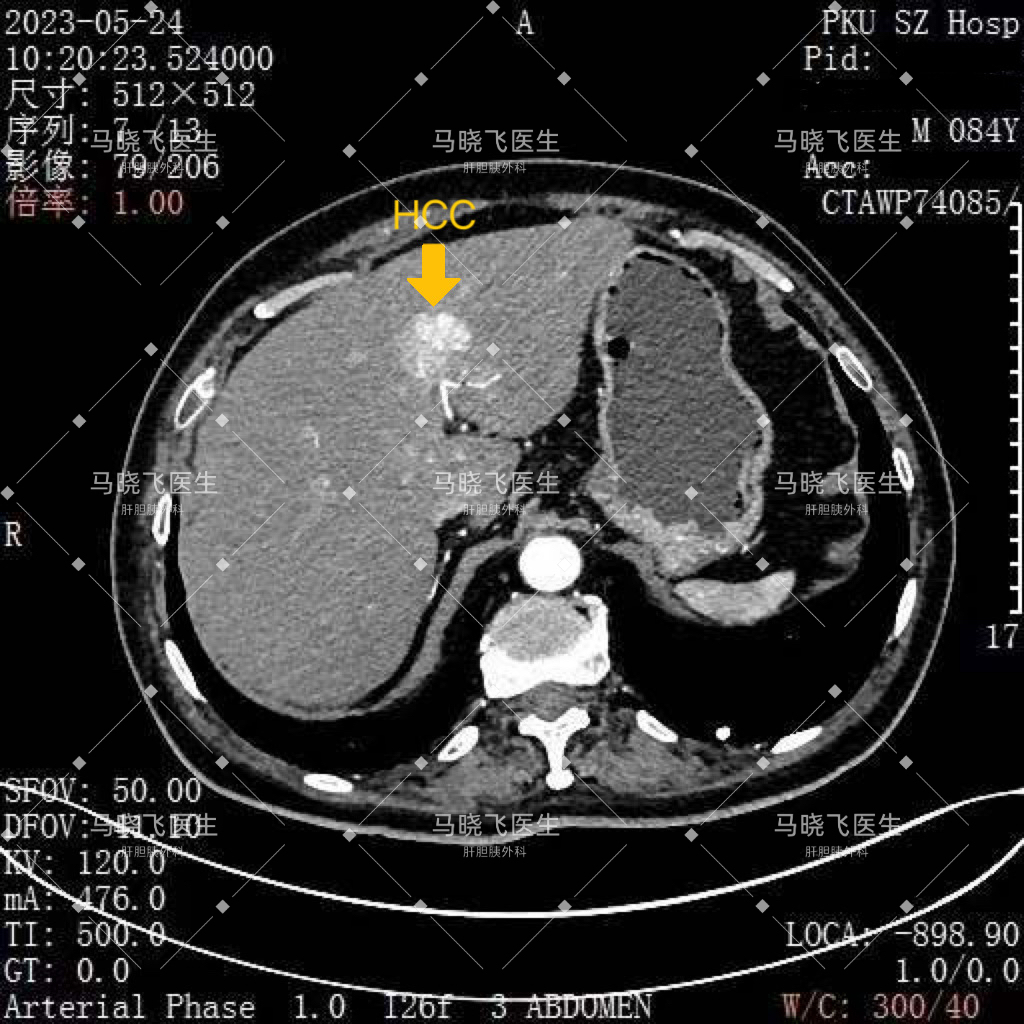

5月底,我们团队就收治了一位患有多种疾病的84岁高龄男性患者。术前影像学提示其“肝S2/4交界处占位,肝癌可能性大”,同时还合并有“胆囊结石”和“右侧腹股沟疝”。不仅如此,他还患有“冠心病”,心脏放过支架,还有多年的“糖尿病”,可以说老爷子是一身的病。

最终,手术顺利完成,术后患者在ICU监护过渡了一天就平稳转回普通病房。术后病理确诊患者为“肝细胞癌”,且为低复发风险,无需进一步治疗,现患者已顺利出院。